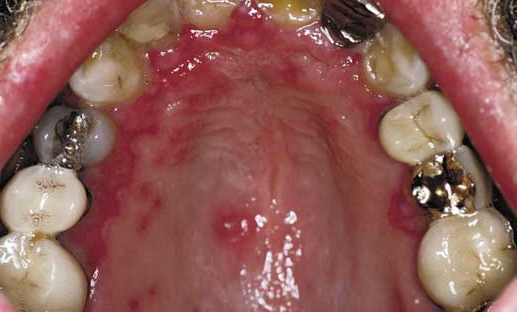

Recurrent HerpeticStomatitis: Secondary

Clinical Presentation

• Intraoralrecurrences characteristically on hard palate or attached gingiva (masticatorymucosa)